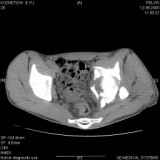

Уважаемые коллеги! Хотелось бы услышать совет по тактике лечения представлленого больного.Поступил после лечения в одном изотделений области. Травма 2,5 месяца назад. После выведенияиз шока был произведен остеосинтез перелома бедра, предплечья, до перевода к нам проводилосьвытяжение по оси шейки бедра за стержень, введенный в большой вертел. На сегодня деформацияригидна, клинически мобильности не определяется. Заранее признателен. P.S. Данный вид травм не включен в перечень "высокотехнологичных операций", направить длялечения по квотам Минздрава очень сложно.

Это обзорные и косые снимки

Привет, Леонид. Оскольчатый высокий двухколонный перелом в такие сроки трогать не надо, т.к. это про такие переломы сказано: "кто с ножом на Ж. пойдет тот в ней и останется...".